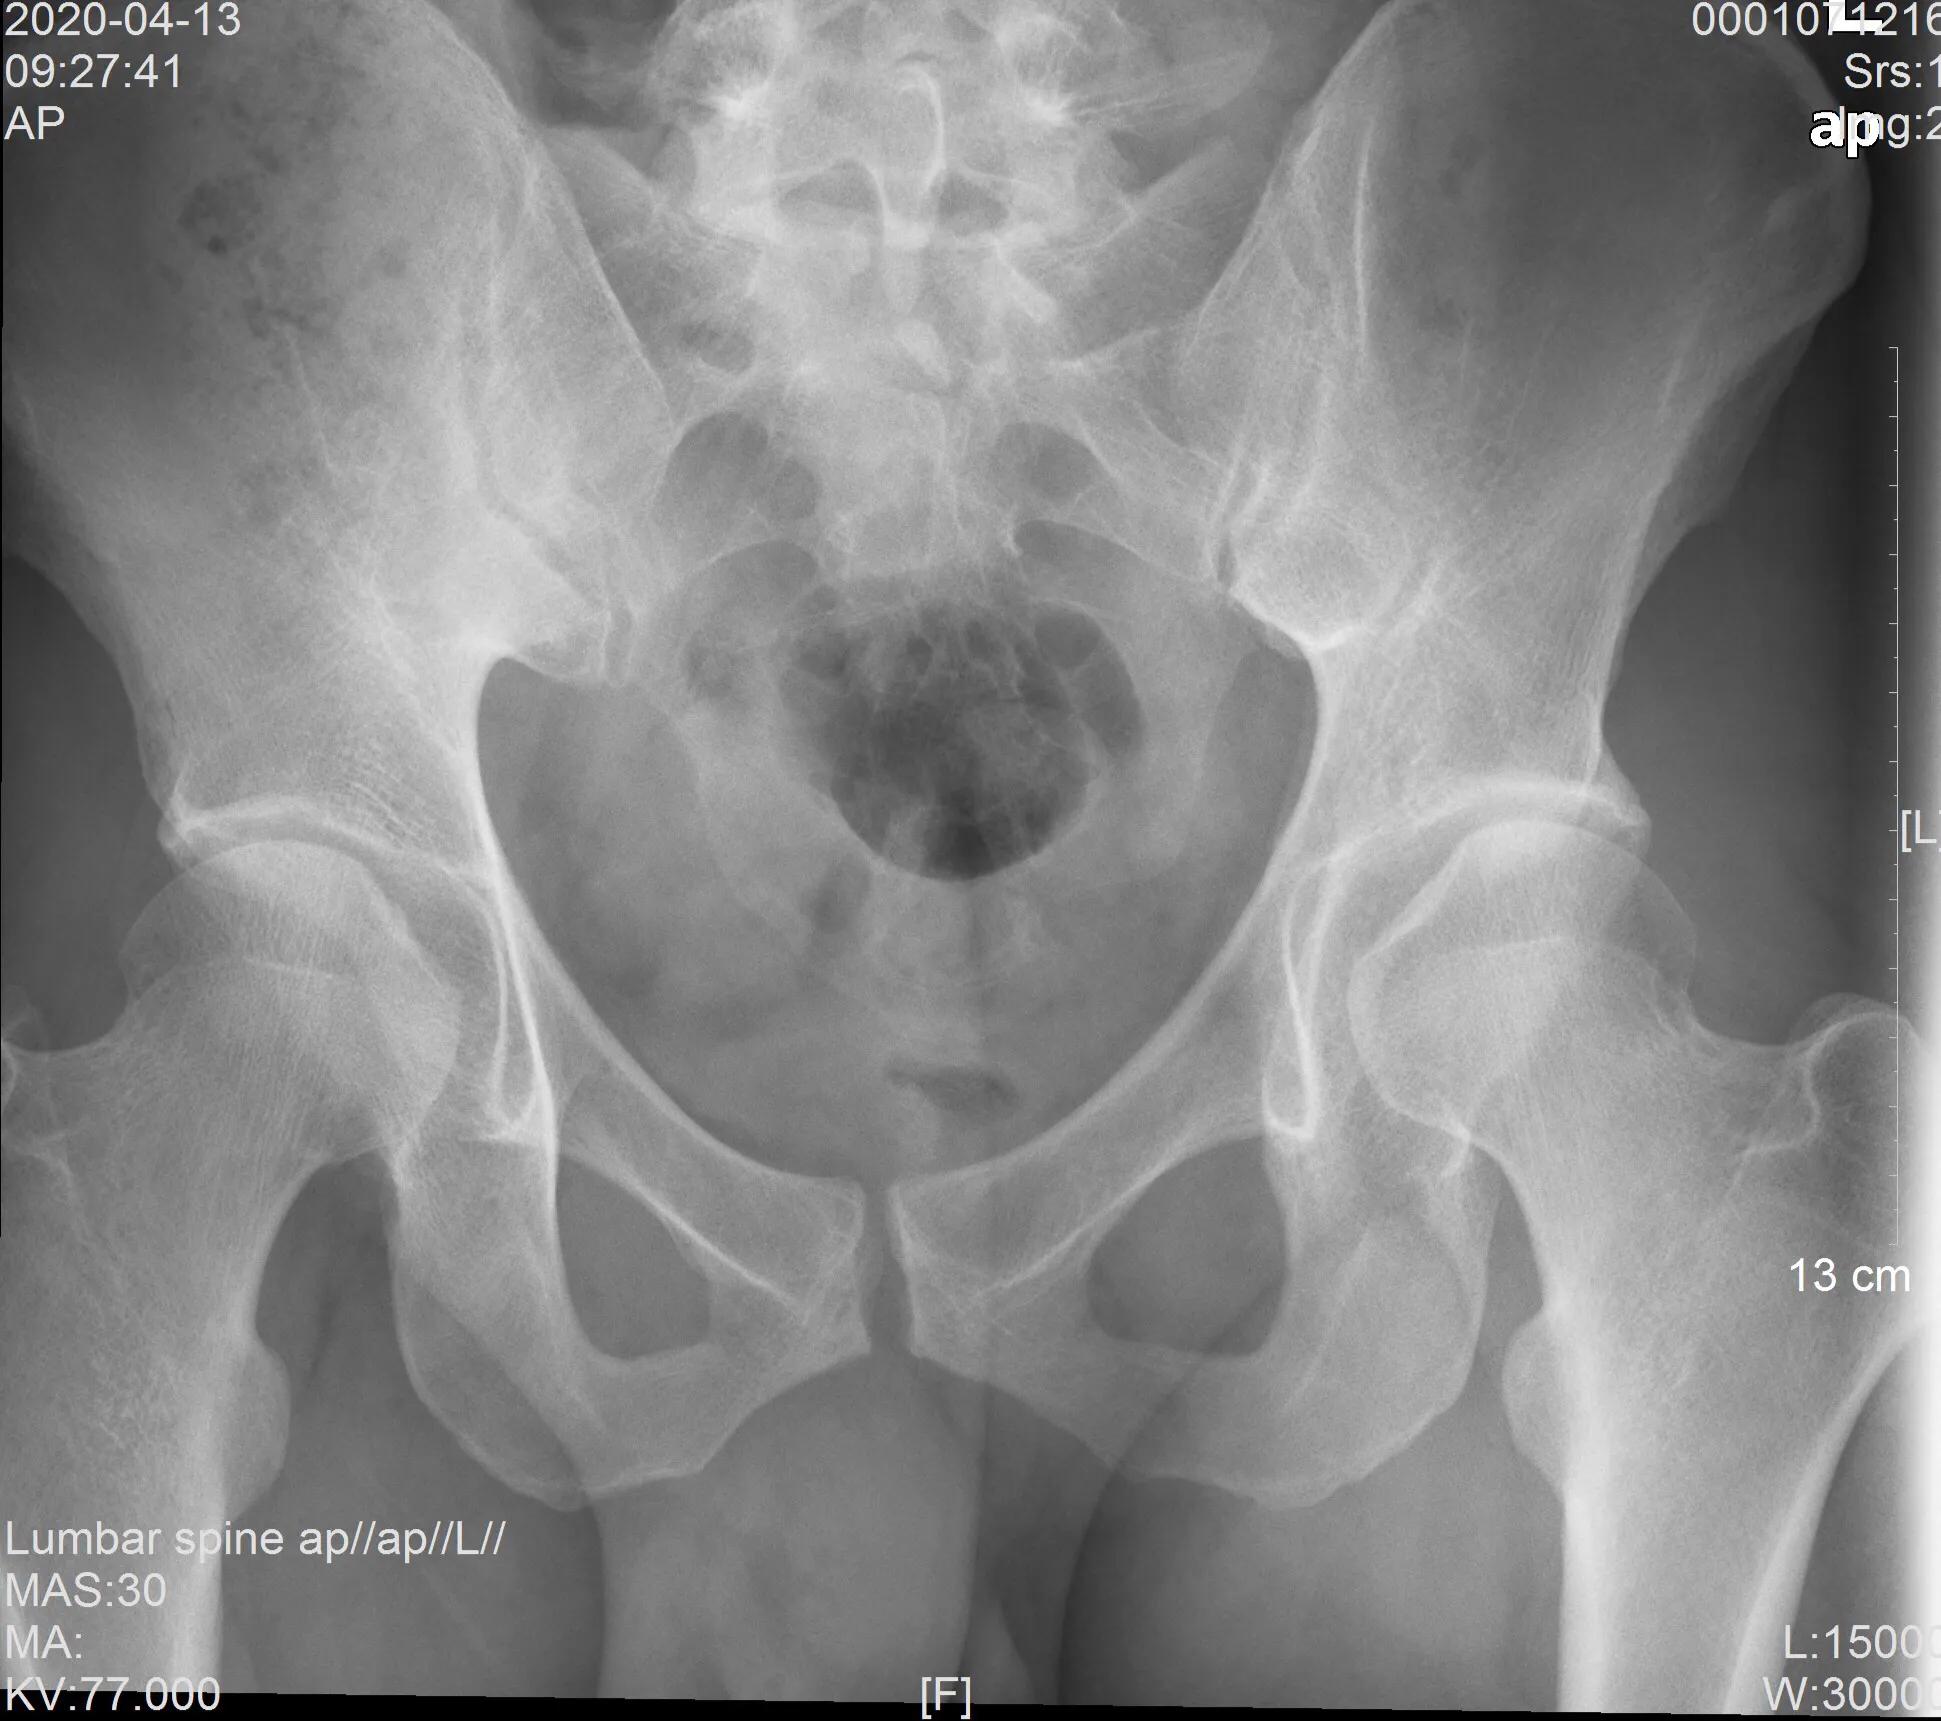

在2020年4月13日凌晨,我在急诊上班,遇到一名患者,男性,30岁,既往体健,主诉:肛门疼痛4小时。体查:肛门胸膝位3点位置见一0.8*0.5cm包块,其内紫色,触痛(未肛诊)。初步诊断:血栓性痔。予止痛对症治疗,嘱到肛肠外科门诊就诊。15日后白天我再次遇到他,这次还是痔疮症状来诊,疼痛加出血。让我感兴趣的是,他13日当天就去肛肠外科门诊就诊,主诊医师告知不是痔疮,请他到中医骨科就诊。他立即到中医骨科就诊,并因骶部疼痛行x线检查,结果如下

考虑骨盆问题而予口服药物解痉止痛对症治疗。于14日无明显改善再次在中医骨科复诊,这次予针灸及中药热敷治疗。15日再次就诊,这次患者出现的问题不单单是疼痛而且体态明显改变,骨盆有移旋,躯体代偿性屈曲旋左,行核磁共振检查。于是就有15日遇到我复查痔疮的问题。我叮嘱患者先到肛肠外科门诊就诊并待核磁共振检查结果后找我复诊。